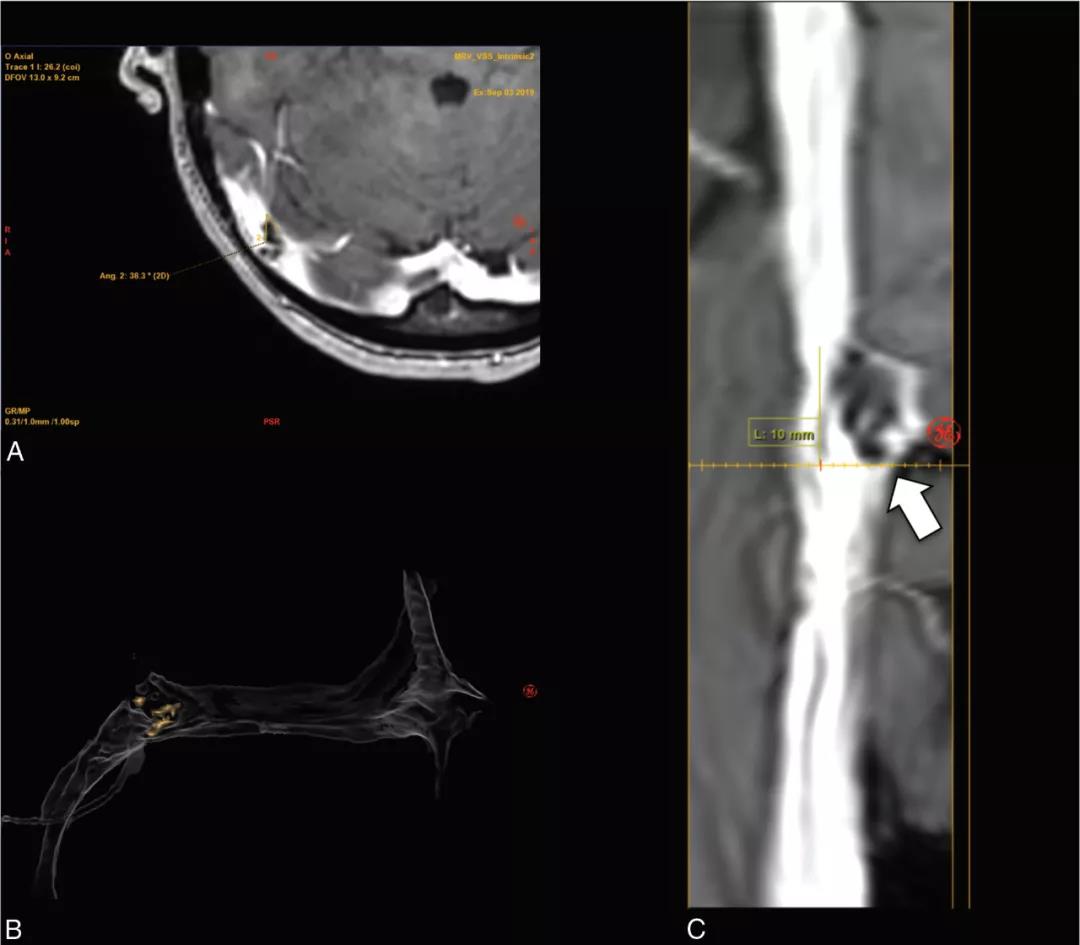

图1 右侧横窦外源性狭窄的 MR 成像。短箭头指向右侧小脑实质位置,长箭头指向枕颅骨(occipital calvaria)位置。A、轴位增强MRV图像;B、三维重建图像;C、右侧横窦-to-近乙状窦的轴位增强原始图像的直线血管重建影像